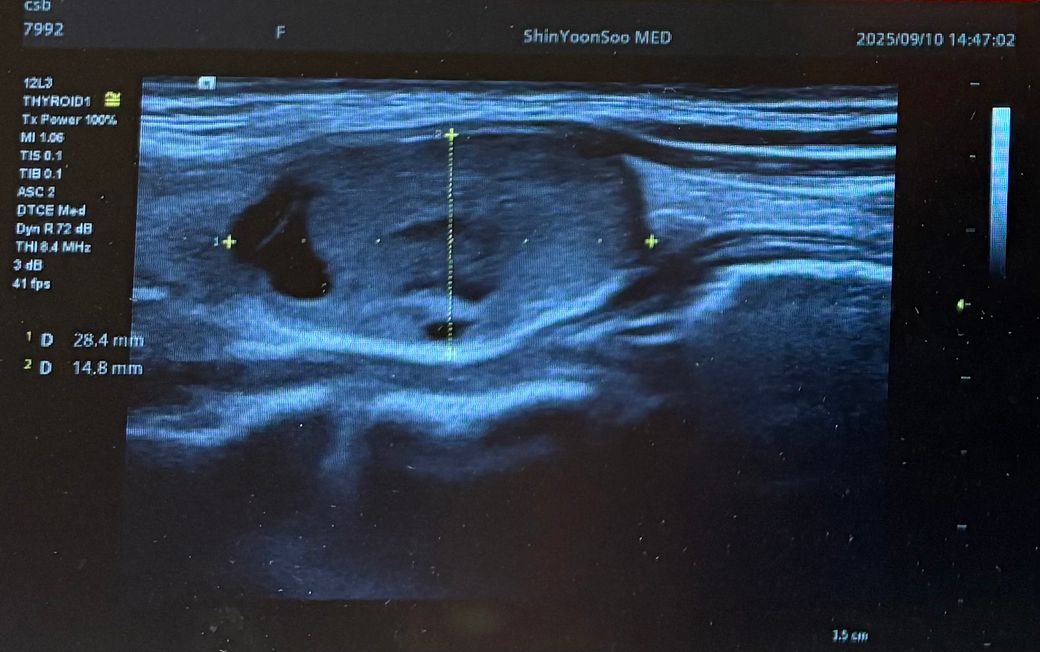

최근 동네 의원에서 갑상선초음파를 보다가 왼쪽 갑상선에 큰 혹 한개와 작은혹 한개가 발견되어 조직검사가 필요할것 같다고 의뢰서를 써주셔서 상급병원으로 예약잡고 저번주에 초진 봤습니다.

Lt 1ower lobe

1.88x1.4x2.84cm mixed nodule Lt middle lobe 1.22x0.37x 0. 49cm의 nodule 소견으로(의뢰서에 적혀있던 내용) 초진 보러가니 초음파 사진만 보시고는 식도와 신경에 들러붙어있고 점점점 커지면서 추후엔 응급수술로 진행될 수 있으니 아직 젊을때 빠르게 수술로 떼어내자고 결론은 수술밖에 없다고 냅다 수술일정 한달뒤로 잡고왔습니다.

왼쪽에 약 3cm가량으로 전체가 혹일거라며 상황이 많이 안좋은거고 위치가 안좋다고 하셔서 다음주에 수술전 검사 받은 후 2주뒤 입원으로 일정이 잡혔는데 보통 세침검사 또는 총생검사 후 수술 여부가 결정되는걸로 알고있는데 ..

• 4번 째 사진